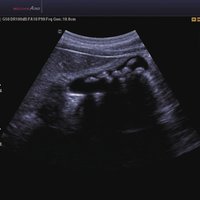

Das Samsung Accuvix A30 ist ein hochwertiges Ultraschallsystem, das mit seiner 3D-Technologie herausragende Ergebnisse ermöglicht. Das Sonographiegerät besitzt 5 Sondenanschlüsse und ist mit 20 unterschiedlichen Schallköpfen kompatibel. Mit dem A30 können Schallköpfe vom Typ Konvex, Mikrokonvex, 3D-Konvex, CW, Phased Array, Linear und Endokavitär verwendet werden. Bei zwei der Sonden handelt es sich um S-VUE Ultraschallsonden, die durch ihre höhere Bandbreite noch feinere Scans erzeugen.

Das Ultraschallsystem hebt sich besonders durch seine 3D-Technologie wie die Face Auto Detection für detaillierte Ultraschallbilder von Föten oder das Volume Shade Imaging, das sich auf die lebensnahe Darstellung von Schattierungen und Hauttönen fokussiert, ab. Mit weiteren wertvollen Technologien wie dem ElastoScan™ werden Tumore schneller erfasst und durch die HD Volumen Bildgebung sowie das DMR+™ eine erstklassige Bildqualität erzielt.

• 2D-Modus

• ElastoScan™ ermöglicht eine genauere Visualisierung von Tumoren und erfasst und dokumentiert Gewebesteifheiten.